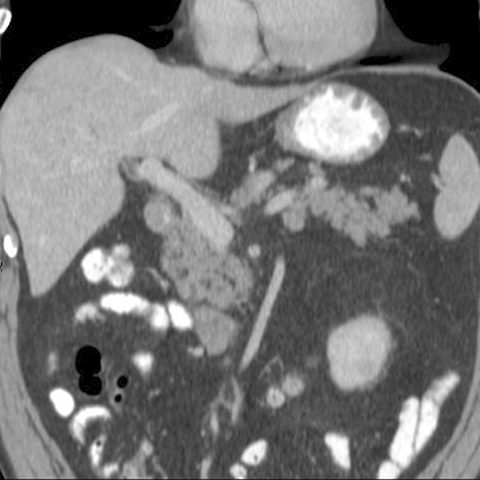

Normal Pancreas, Coronal CT [3 of 3]